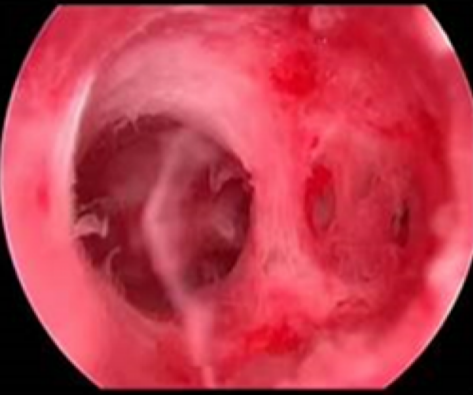

宫腔粘连图

姜女士听到这个消息后感到既震惊又害怕。她不明白自己一直身体健康,怎么会突然患上这样的病,怪不得一直备孕不成功。汪医生耐心地向她解释:正常的子宫有些像梨,倒三角形,子宫最靠近里面的部分覆盖着一层子宫内膜,子宫内膜周期性剥脱会形成月经。宫腔粘连使宫腔部分或全部闭锁,或子宫颈内口闭锁的现象,通常会存在着部分子宫内膜的缺损,子宫前后或者左右壁粘合在一起了。宫腔粘连可能由多种因素引起,包括既往的子宫手术、感染等。李女士回想起两年前的一次清宫手术,可能就是导致宫腔粘连的原因。

汪医生建议姜女士接受宫腔镜下粘连分离术。汪医生介绍说宫腔镜可以在直视下观察宫腔情况,对宫腔疾病作出准确判断,还可以评估导致不孕不育的宫腔因素。并在诊断同时给与治疗,集诊断与治疗于一体。姜女士接受了汪医生的建议。手术过程中,汪医生通过宫颈插入宫腔镜,观察宫腔内的情况,评估粘连的范围和程度。随后在宫腔镜的指导下,汪医生使用专用的宫腔镜器械对粘连区进行切割和剪除,分离粘连并剔除疤痕组织,手术非常成功。术后,给与姜女士中西医结合药物治疗,帮助子宫内膜修复。